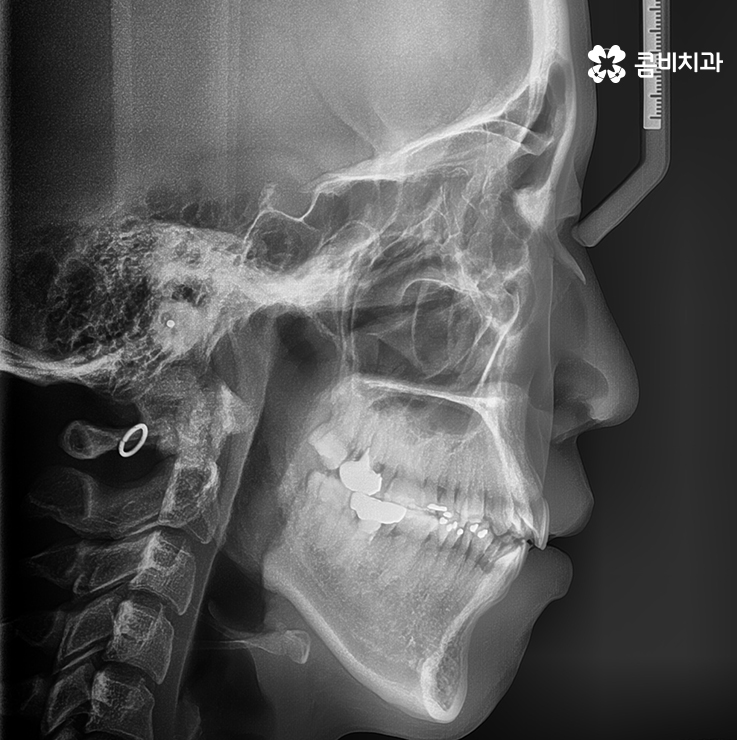

옆모습으로 볼때 돌출된 치아로 인한 돌출입 상태

(좌) 얼굴을 고려하여 돌출입을 개선하는 치료 계획을 세움, (우) 사랑니 발치와 상악 14,24 / 하악 34,44 치아 발치 진행

심한 돌출입은 아니었기 때문에 비수술적인 방법으로 치료 진행